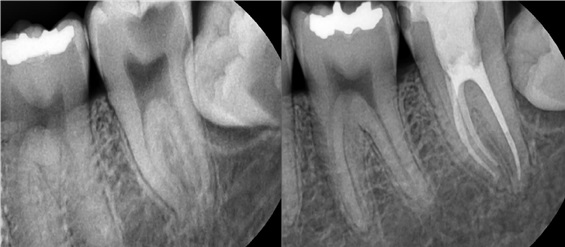

치료전후사진